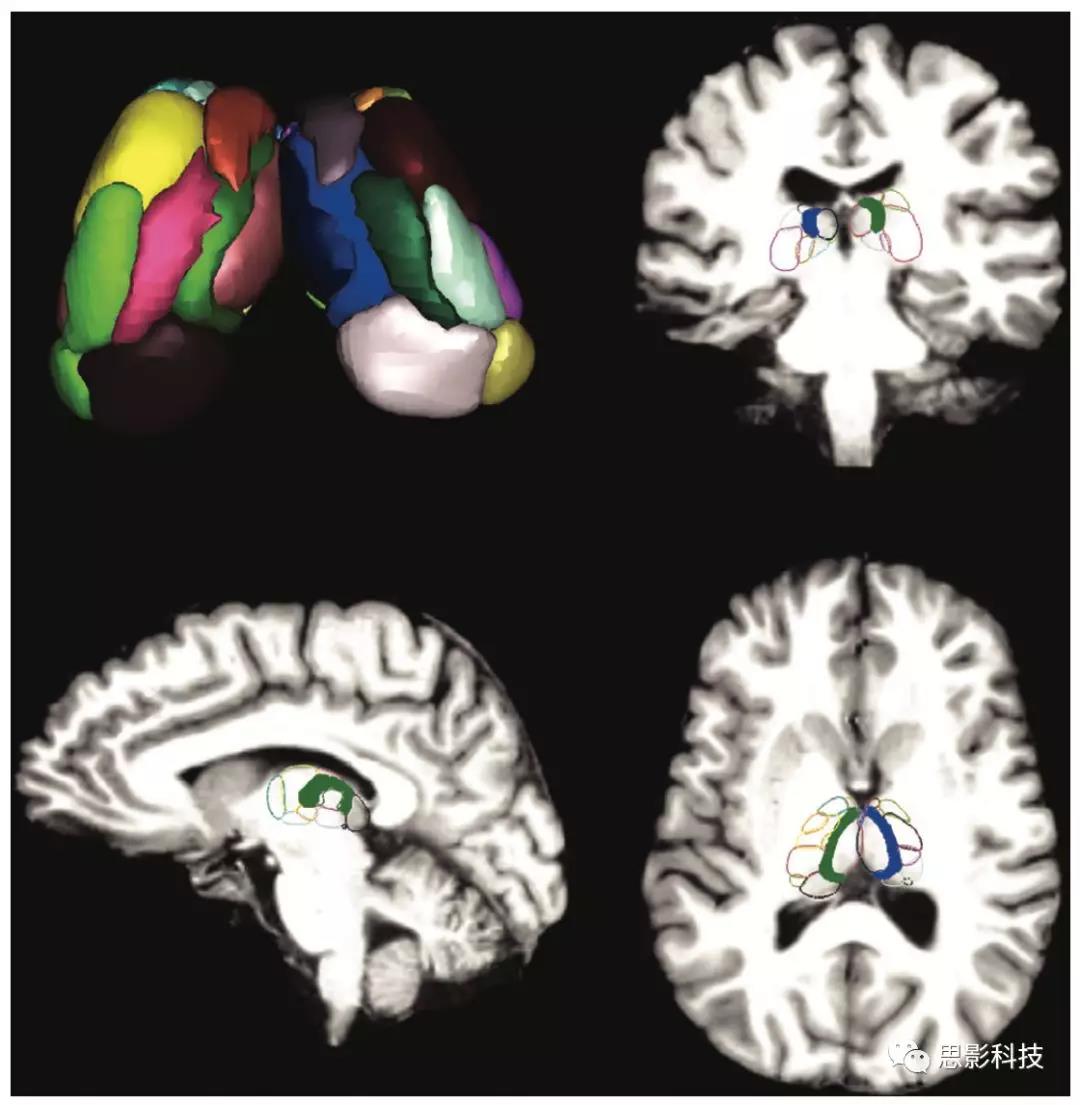

接下來,作者研究了單個(gè)丘腦核與枕葉內(nèi)側(cè)之間的連接,特別關(guān)注了丘腦中央外側(cè)核CL(2中突出顯示的部分),因?yàn)樗?b>視覺空間注意力方面的潛在作用,并且它可能參與了癲癇邊緣網(wǎng)絡(luò)。在這些分析中,使用了19個(gè)雙側(cè)(38個(gè))丘腦核的自定義圖譜(2)。結(jié)果顯示,對(duì)照組CL和枕葉內(nèi)側(cè)之間存在正常的負(fù)相關(guān),而TLE患者則沒有這種相關(guān)性(3a;p<0.001,配對(duì)t檢驗(yàn),未校正)??偟膩碚f,在雙側(cè)丘腦核中,CL顯示出患者與對(duì)照組在枕葉中葉連通性上的最大差異。鑒于CL是一個(gè)對(duì)維持皮質(zhì)激活和覺醒很重要的層內(nèi)核,主要的傳入投射起源于MR/PBC腦干ARAS核,因此接下來測(cè)量了所有參與者中MR/PBCCL之間的功能連接。與對(duì)照組相比,TLE患者的MR/PBCCL之間的功能連接發(fā)生了改變,在患者中觀察到更多的陽性連接(3b;p=0.003,配對(duì)t檢驗(yàn),未校正)。總之,這些發(fā)現(xiàn)表明了TLE中的丘腦覺醒網(wǎng)絡(luò)存在異常連接。此外,為了確保研究結(jié)果的可靠性,作者檢查了術(shù)前患者和相匹配的對(duì)照組的第一和第二靜息態(tài)期的功能連接值的相關(guān)性。結(jié)果提示,每個(gè)靜息狀態(tài)下的丘腦連通性(整個(gè)丘腦和CL)均相關(guān)(ρ= 0.54–0.78,Spearman’s rhop <0.01)。同時(shí)還針對(duì)每個(gè)靜息態(tài)重復(fù)了術(shù)前患者與匹配對(duì)照的連通性測(cè)量值的比較,提示與前面具有相同的關(guān)系(配對(duì)t檢驗(yàn),p <0.01

2:圖中所示的是活動(dòng)形態(tài)模型的丘腦圖,左上為23個(gè)雙側(cè)丘腦內(nèi)核(46個(gè)核)。排除4個(gè)掩膜小于2個(gè)體素的核團(tuán),使用19個(gè)雙側(cè)核(38個(gè))進(jìn)行分析。MRI冠狀面、矢狀面和軸面顯示相同的圖譜,該圖譜覆蓋在標(biāo)準(zhǔn)的蒙特利爾神經(jīng)病學(xué)研究所的空間大腦上,每個(gè)核都用顏色勾勒出輪廓。在冠狀面、矢狀面和軸面中,CL層內(nèi)丘腦核團(tuán)以藍(lán)色和綠色顯示。對(duì)于涉及整個(gè)丘腦的分析,使用哈佛-牛津圖譜里的整個(gè)丘腦,使用進(jìn)行連接分析時(shí),則使用CL標(biāo)識(shí)。CL:丘腦中央外側(cè)核。